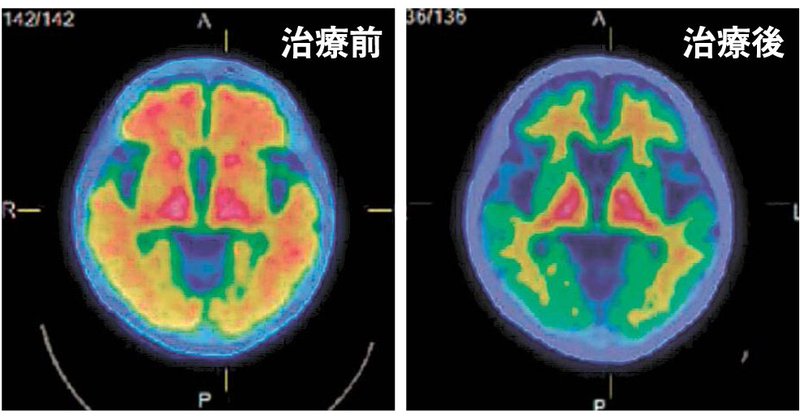

アミロイドβが完全に除去されたとのことだけど、認知機能はもとに戻ったのかな? https://t.co/LfxQ3nzOAw

金大附属病院は1日までに、アルツハイマー型認知症の新治療薬「…